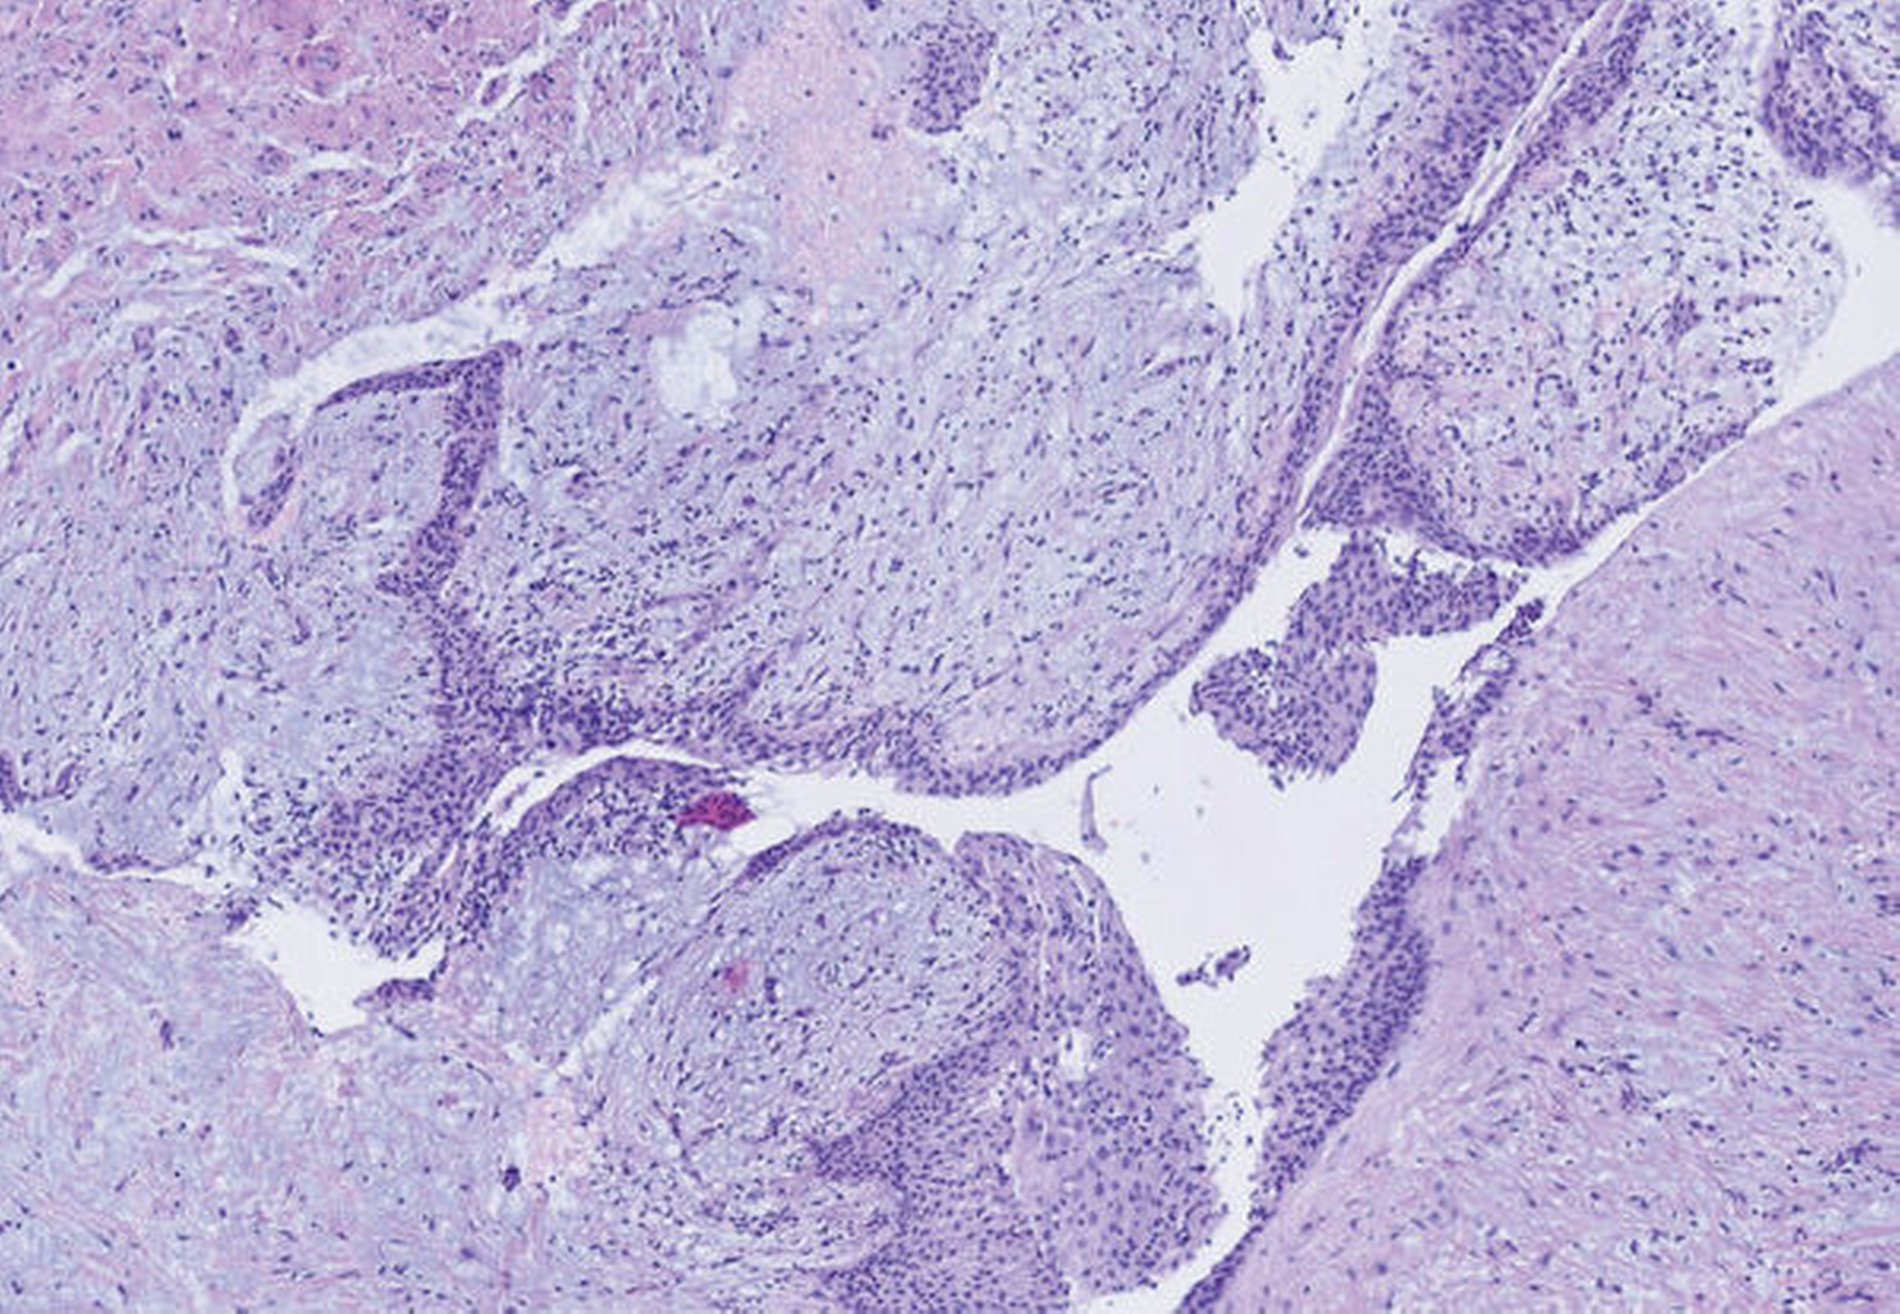

Die Tamponade konnte nach fünf Tagen entfernt und der fertiggestellte Obturator durch die Kollegen der Kieferorthopädie eingegliedert werden. Die histopathologische Aufbereitung zeigte eine Zyste mit Auskleidung durch Plattenepithel, fibrosiertem Bindegewebe und lymphozytärer Infiltration – vereinbar mit dem klinischen Bild einer follikulären Zyste (Abbildung 7).